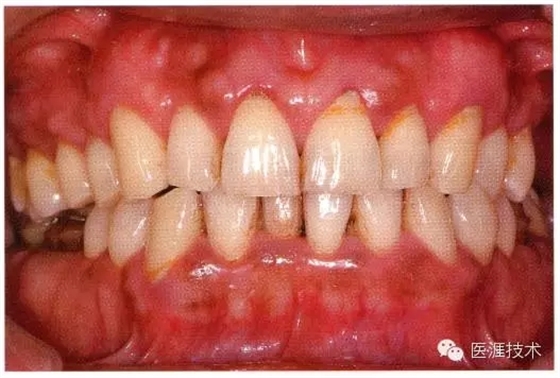

健康且正常的牙周組織臨床圖像

50歲女性的健康口腔內(nèi)部

圖為50歲女性,無特殊全身疾病,不抽煙。持續(xù)保養(yǎng)6年。無填充物等問題,依照患者本人要求持續(xù)觀察。牙周組織臉頰側(cè)雖見部分萎縮,但X線牙片顯示牙間無骨吸收現(xiàn)象,保持著比較健康的狀態(tài)。